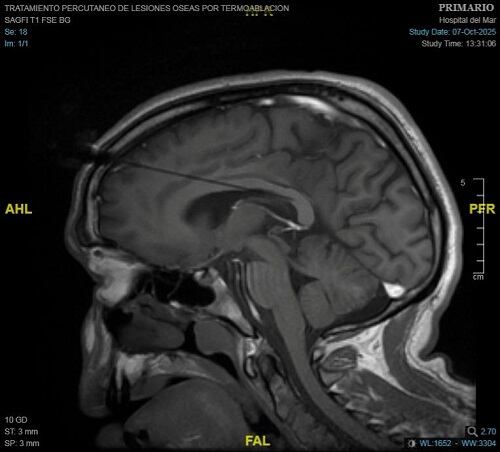

La intervención ha consistido en quemar parte del cuerpo calloso del cerebro para limitar la comunicación entre las fibras nerviosas que conectan ambos hemisferios. La callosotomía, como se denomina este procedimiento, se ha realizado tradicionalmente mediante un abordaje quirúrgico abierto, por lo que la intervención con láser evita que el cirujano lleve a cabo un corte grande en la piel para tener acceso directo al cerebro.

El paciente, que pasó por quirófano el pasado 7 de octubre, presentaba un tipo de epilepsia resistente al tratamiento farmacológico convencional. Al mismo tiempo, no podía ser intervenido de cirugía curativa. Tras un proceso de planificación con imágenes 3D junto al equipo de la Unidad de Epilepsia, encabezado por el Dr. Rodrigo Rocamora, se seleccionó el área del cuerpo calloso del cerebro a tratar para interrumpir la comunicación entre los dos hemisferios cerebrales. El equipo liderado por el Dr. Carlo Marras, jefe del Servicio de Neurocirugía, junto a la Dra. Nazaret Infante, médica adjunta del mismo servicio.

Según explica el hospital en un comunicado, para la realización de esta técnica "se colocan de dos a tres sondas láser a través de accesos milimétricos en el cráneo que servirán, con monitorización constante de imágenes de resonancia magnética, para realizar la intervención y obtener el resultado esperado". Así, gracias las altas temperaturas que consigue alcanzar el láser y con ayuda de un sistema robótico, se actúa sobre la zona concreta del cuerpo calloso seleccionada sin afectar las zonas del cerebro circundantes.